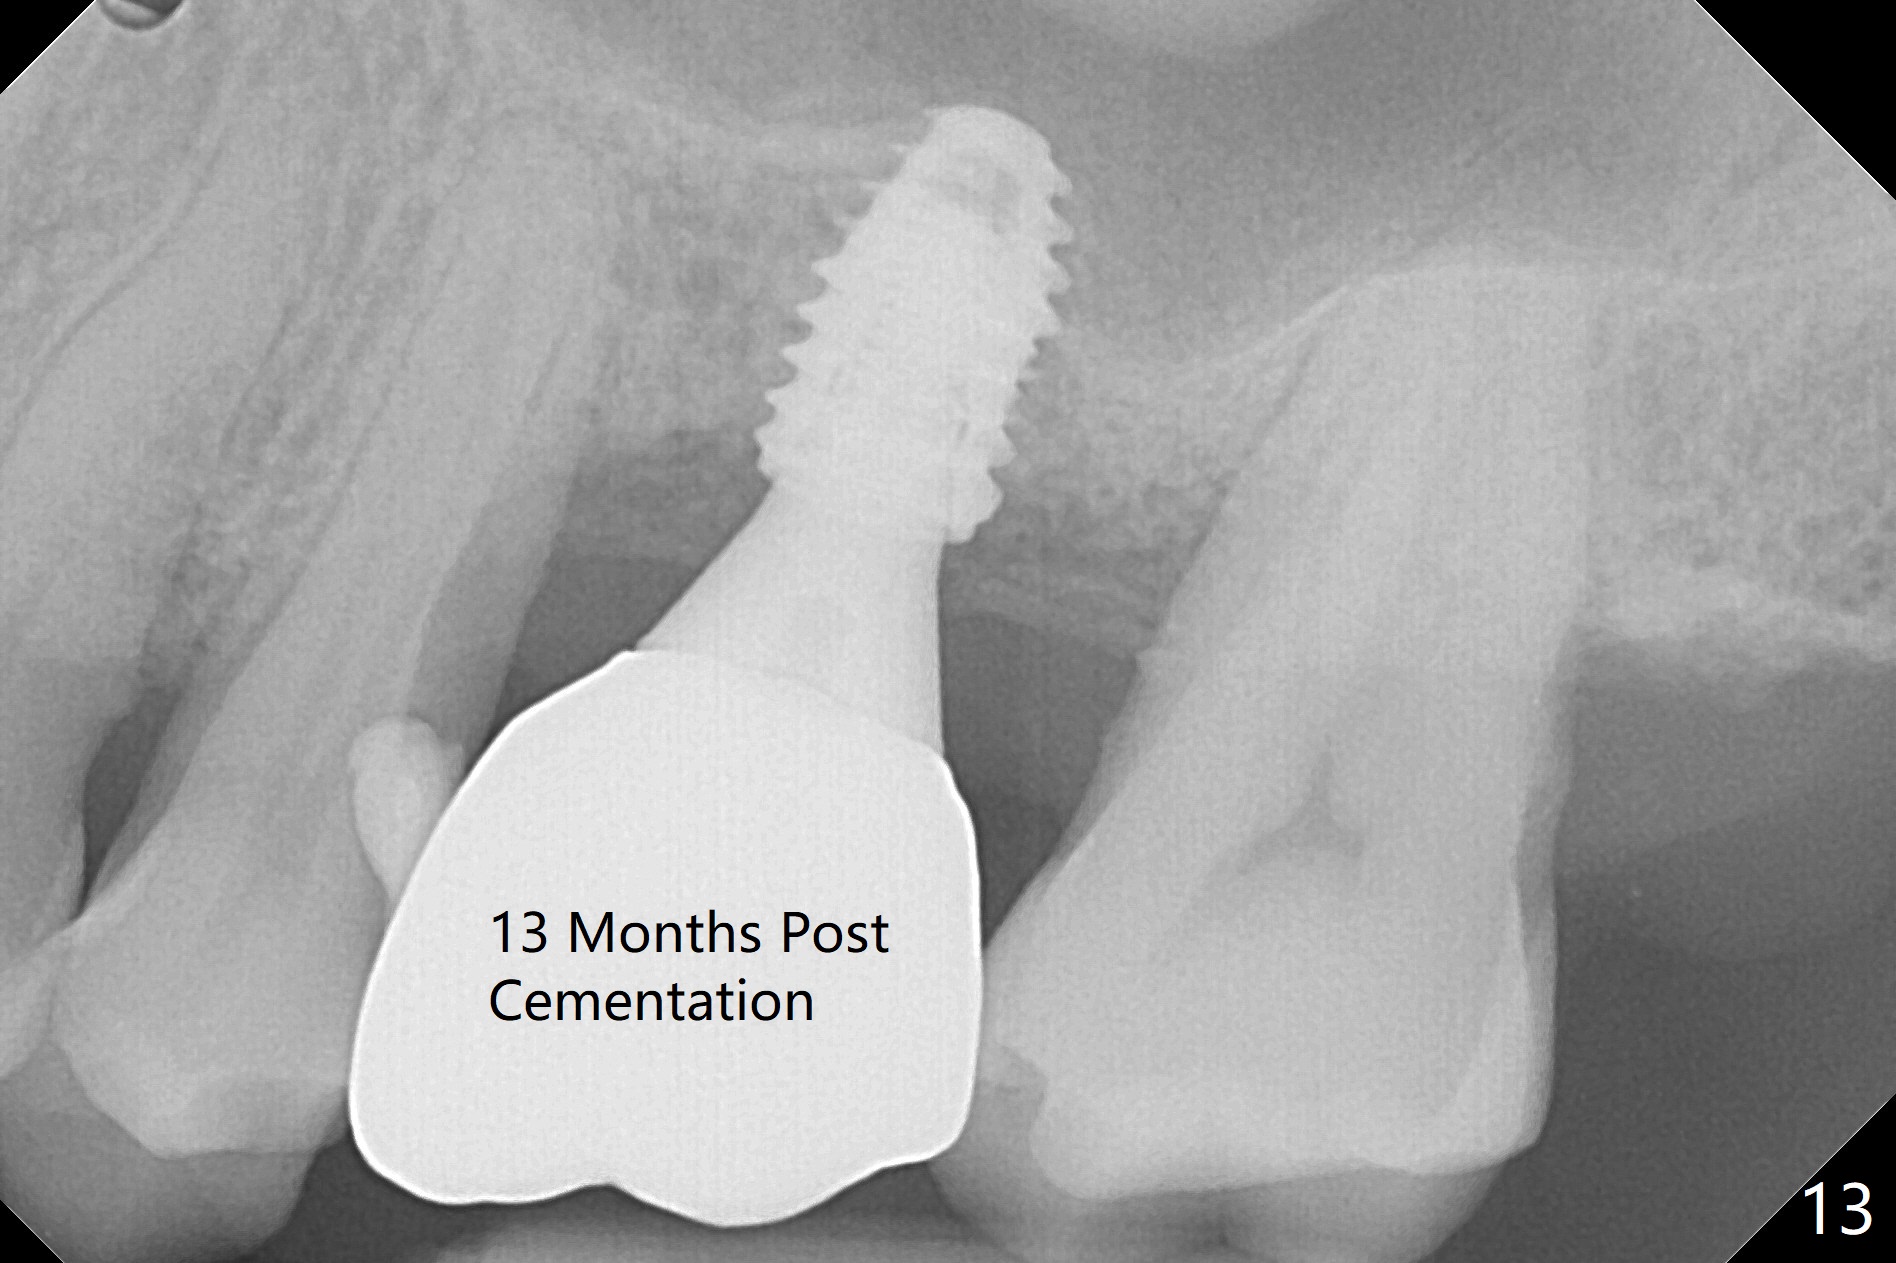

Trajectory of sinus lift without guide at #14 is off (Fig.1 (Magic Sinus Lifter (L) for 9 mm (gingival level)) and needs to be corrected (Fig.2 long line) by re-using 4.8 mm Magic Drill. Following placement of PRF membrane and Demineralized Cortical Allograft (.125-.850 mm) for sinus lift (Fig.3 black dashed line), a 4x10 mm dummy implant is placed with off trajectory. The latter will be fixed by using Lindmann bur to remove the bone distal (Fig.4). The result is less satisfactory with placement of 4.5x10 mm dummy implant (Fig.5). It appears necessary to initiate a new osteotomy (Fig.6 long black line). In fact the result is appealing (Fig.7). The final implant (5x7.3 mm) seems to be placed ideally shown by PA (Fig.8) and BW (Fig.9). Immediately postop CT demonstrates distal defect (Fig.10 *;3-D) and supracrestal placement palatal (Fig.11 P; coronal section). More allograft is then placed in these 2 areas. In all, it is difficult to establish a correct osteotomy without guide. The patient return for uncover 3.5 months postop, although there is a small hole in the middle of the incision (Fig.12). The crown/abutment becomes loose less than 1 month post cementation when the patient chews something tough. It is more related to the unfavorable implant/crown ratio. It is loose again 2 months later. Screw driver is buried inside the abutment with plumber tape. When it is loose for the 3rd time 13 months post cementation, the existing screw driver with a created slot (for retention) is buried without plumber tape after retorque at 35 Ncm (Fig.13). A tissue-level implant should have been used.